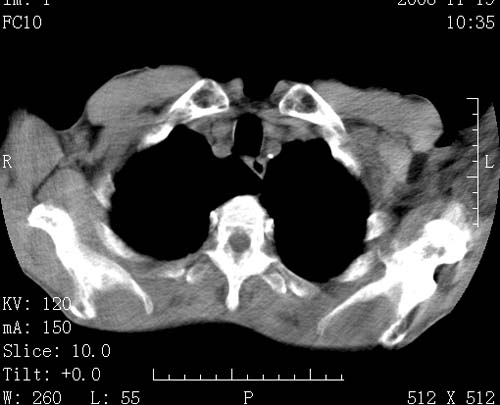

标题: CT16691:m 67 胃镜确诊食管下段及贲门癌 [打印本页]

标题: CT16691:m 67 胃镜确诊食管下段及贲门癌

术前查体,双肺部结节是转移?结核?请点评

1)符合食管癌表现。2)两肺及纵隔淋巴结多发性转移瘤。3)左肺上叶舌段及两肺下叶炎症感染。